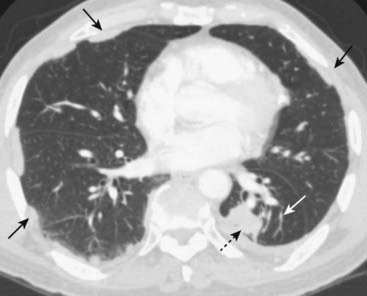

image

Figure 5-7 Subsegmental atelectasis.

Close-up view of the lung bases demonstrates several linear densities extending across all segments of the lower lobes, paralleling the diaphragm (solid black arrows). This is a characteristic appearance of subsegmental atelectasis, sometimes also called discoid atelectasis or platelike atelectasis. The patient was postoperative from abdominal surgery and was unable to take a deep breath. The atelectasis disappeared within a few days after surgery.

Figure 5-8 Compressive (passive) atelectasis.

Passive compression of the lung can occur either from a poor inspiratory effort (A), which is manifest as increased density at the lung bases (solid white arrow) or secondary to a large pleural effusion or pneumothorax (B). Axial CT scan of the chest showing only the left hemithorax (B) demonstrates a large left pleural effusion (solid black arrow). The left lower lobe (dotted black arrow) is atelectatic, having been compressed by the pleural fluid surrounding it.

imagePitfall: Be suspicious of compressive atelectasis if the patient has taken less than an 8 posterior-rib breath.

Solution: Check the lateral projection for confirmation of the presence of real airspace disease at the base.

When caused by a large effusion or pneumothorax, the loss of volume associated with compressive atelectasis may balance the increased volume produced by either fluid (as in pleural effusion) or air (as in pneumothorax).

In an adult patient with an opacified hemithorax, no air bronchograms and little or no shift of the mobile thoracic structures, it is important to suspect an obstructing bronchogenic carcinoma, perhaps with metastases to the pleura (Fig. 5-9).

Round atelectasis

This form of compressive atelectasis is usually seen at the periphery of the lung base and develops from a combination of prior pleural disease (such as from asbestos exposure or tuberculosis) and the formation of a pleural effusion that produces adjacent compressive atelectasis.

When the pleural effusion recedes, the underlying pleural disease leads to a portion of the atelectatic lung becoming “trapped.” This produces a masslike lesion that can be confused for a tumor.

On CT scan of the chest, the bronchovascular markings characteristically lead from the round atelectasis back to the hilum producing a comet-tail appearance (Fig. 5-10).

Figure 5-10 Round atelectasis, left lower lobe.

There is a masslike density in the left lower lobe (dotted black arrow). The patient has underlying pleural disease in the form of pleural plaques from asbestos exposure (solid black arrows). There are comet-tail shaped bronchovascular markings that emanate from the “mass” and extend back to the hilum (solid white arrow). This combination of findings is characteristic of round atelectasis and should not be mistaken for a tumor.